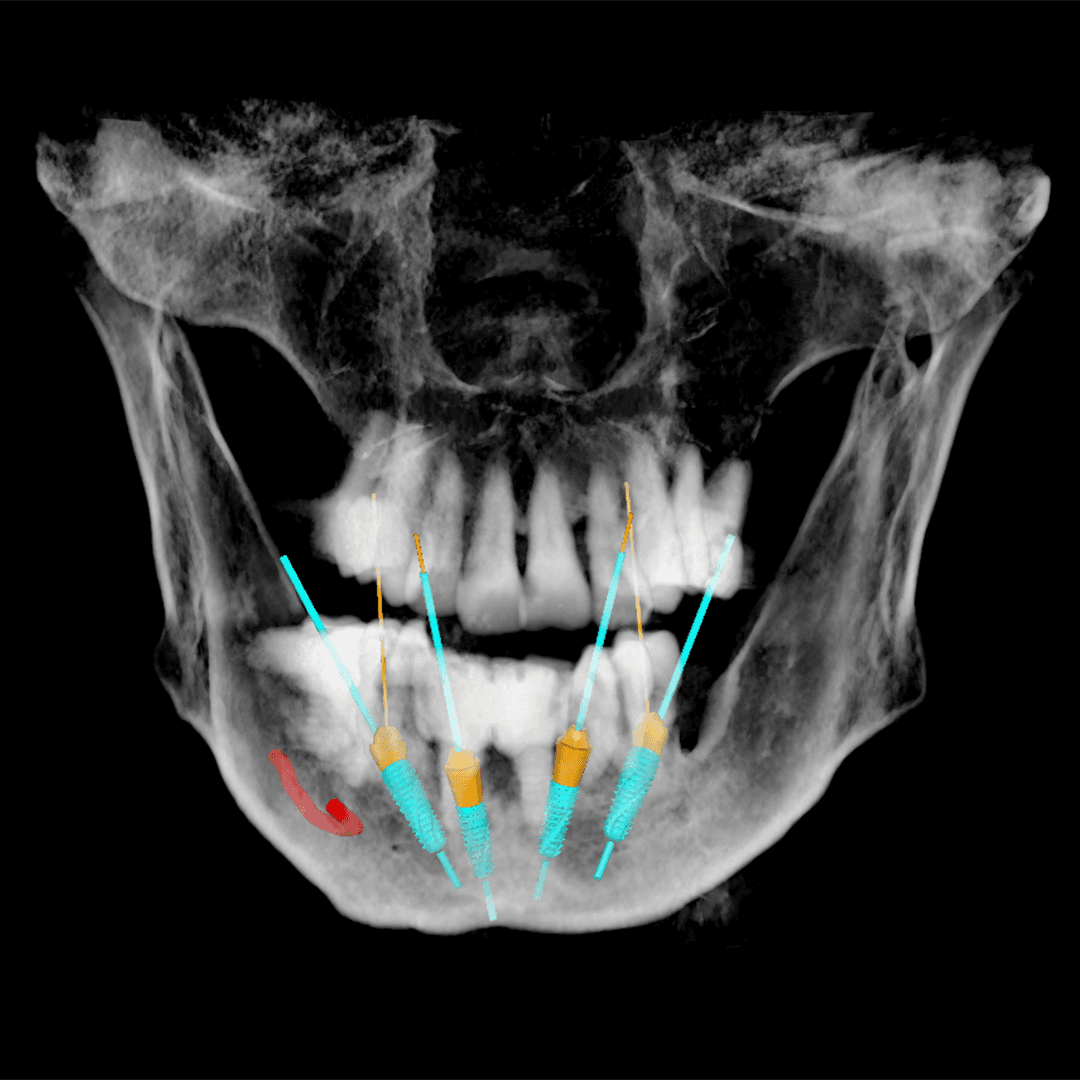

Implant Planning

We will utilize your CBCT scan and diagnostic models/.STL files to develop a preliminary treatment plan. Following this, you will have the option to determine the final implant placement.

After you confirm the final treatment plan, we create the appropriate surgical guide and proceed to 3D printing using high-end printers, or you can provide your own .STL file.